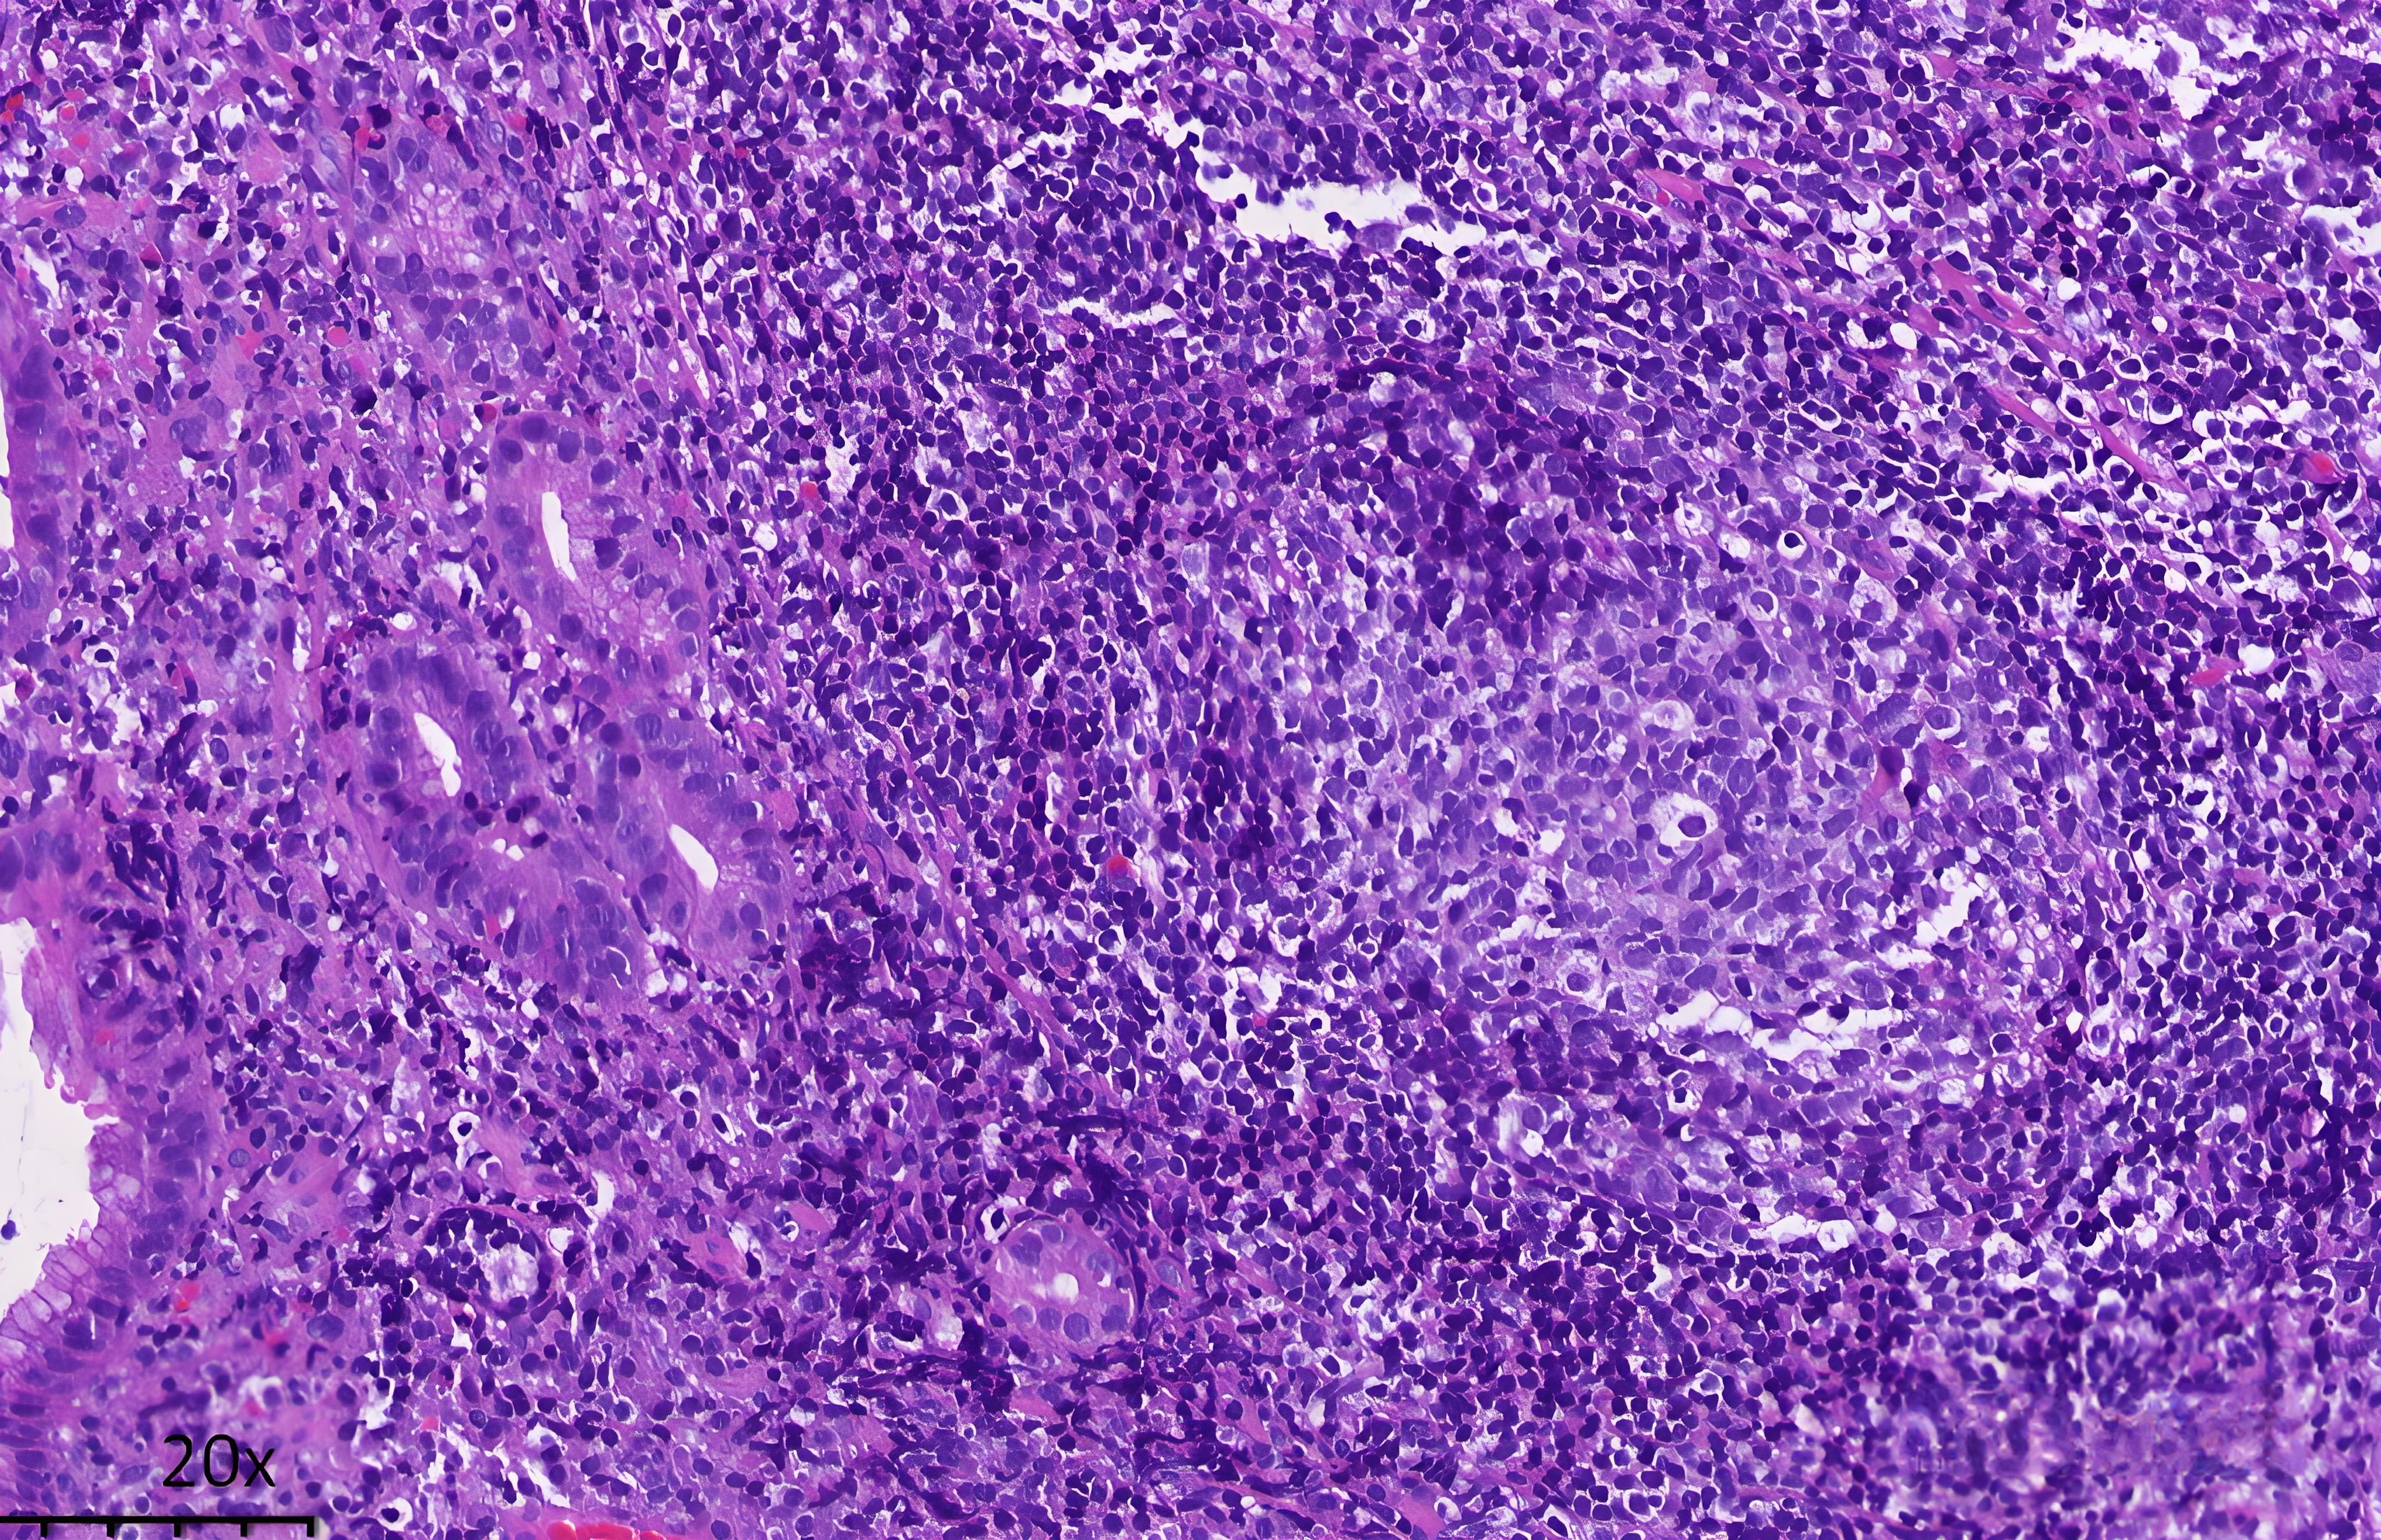

病理检查是诊断的金标准。显微镜下,肿瘤细胞会呈现特征性的"边缘区细胞"增生,并可能形成"淋巴上皮病变"(即淋巴细胞浸润并破坏胃腺体)。

通过CD20、CD5、CD10、CD23等标记物可以确认其B细胞来源,并与其他类型的小B细胞淋巴瘤进行鉴别-7。胃MALT淋巴瘤通常表现为CD20阳性、CD5阴性、CD10阴性、CD23阴性。